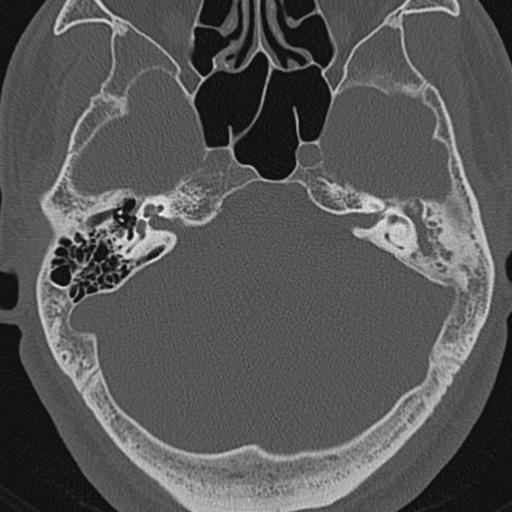

以下是引用zxl51642在2009-8-25 13:37:00的发言:[br]1、左侧慢性硬化型中耳乳突炎(中耳鼓室腔及听小骨受累),并胆脂瘤形成;2、左侧外耳道软组织密度影填塞,考虑炎性肉芽肿,建议结合临床;3、右侧颈静脉窝较左侧明显扩大,不排除颈静脉球瘤,建议mr进一步检查。

以下是引用随光逐影在2009-8-25 19:05:00的发言:[br]1)左侧慢性中耳乳突炎(肉芽肿或胆脂瘤形成),左侧外耳道炎性肉芽肿。2)右侧颈静脉球高位。